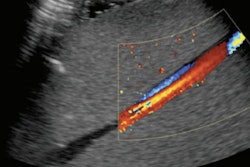

3D ultrasound overcomes these limitations because it offers a more complete view of hip geometry than 2D ultrasound and also because it is automated, Zonoobi and colleagues wrote. The modality was first suggested for the diagnosis of DDH in the 1990s, but only recently has transducer technology evolved enough to make the use of 3D ultrasound for this application feasible.

For their study, Zonoobi and colleagues added 3D ultrasound to conventional 2D ultrasound exams of 1,728 infants (mean age, 67 days) to evaluate the children for DDH; the exams were performed between January 2013 and December 2016. Custom software automatically calculated measures such as 3D posterior and anterior alpha angle and osculating circle radius. Of the infants imaged, 1,347 were normal, 140 were borderline for the condition, and 241 were dysplastic.